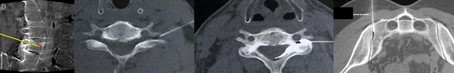

Minimal-invasive Schmerztherapie Wirbelsäule

Im Rahmen der Schmerztherapie der Wirbelsäule nutzen wir minimal-invasive Infiltrationsverfahren unter bildgestützter CT-Kontrolle, um schmerz- und entzündungshemmende Medikamente exakt an den Ort der Schmerzquelle zu bringen und können so die Schmerzleitung effektiv unterbrechen.

Letzteres geschieht bevorzugt an den kleinen Wirbelgelenken (als Facettengelenksblockade) bei Patientinnen und Patienten mit chronischen Rückenschmerzen. Die Umspülung der Nervenwurzeln, welche durch die Zwischenwirbellöcher in den Wirbelkanal eintreten, dient als "periradikuläre Therapie" der Behandlung von meist in die Extremitäten ausstrahlenden Schmerzen bei Bandscheibenvorfällen oder degenerativen, knöchernen Engen.